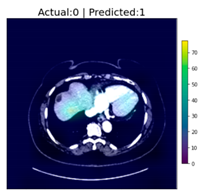

| Image Number | Overlaid Image | Deep Lesion Label | CNN Result | Clinical Radiologist’s Diagnosis | Grad-CAM Helpfulness |

|---|---|---|---|---|---|

| 1 | ![]() | Has Tumor | Has Tumor | Has Tumor | Some |

| 2 | ![]() | Has Tumor | Has Tumor | Has Tumor | Yes |

| 3 | ![]() | Has Tumor | Has Tumor | Has Tumor | Yes |

| 4 | ![]() | Has Tumor | Has Tumor | Has Tumor | Yes |

| 5 | ![]() | Has Tumor | Has Tumor | Has Tumor | Yes |

| 6 | ![]() | No Tumor | Has Tumor | Has Tumor | Yes |

| 7 | ![]() | Has Tumor | Has Tumor | Has Tumor | Yes |

| 8 | ![]() | Has Tumor | Has Tumor | Has Tumor | Yes |

| 9 | ![]() | Has Tumor | Has Tumor | Has Tumor | Some |

| 10 | ![]() | Has Tumor | Has Tumor | Has Tumor | Yes |

| 11 | ![]() | Has Tumor | Has Tumor | No Tumor (Cyst) | Some |

| 12 | ![]() | Has Tumor | Has Tumor | Has Tumor | Yes |

| 13 | ![]() | Has Tumor | Has Tumor | No Tumor | Yes |

| 14 | ![]() | Has Tumor | Has Tumor | No Tumor (Inflammation of the Biliary Tract) | Some |

| 15 | ![]() | No Tumor | Has Tumor | No Tumor (Cyst) | Some |

| 16 | ![]() | Has Tumor | Has Tumor | Has Tumor | Yes |